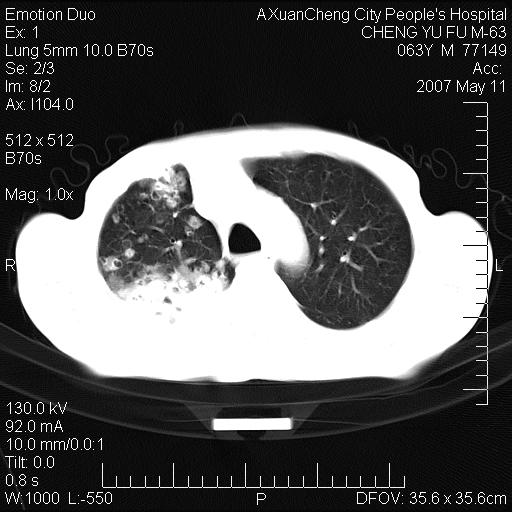

以下是引用小初学者在2007-5-11 19:32:00的发言:[br]1、首先考虑干酪性肺炎支气管播散[br]2、支气管肺泡癌待排

以下是引用zhangzhongshou在2007-5-11 19:30:00的发言:[br]细支气管肺泡癌可能性大。